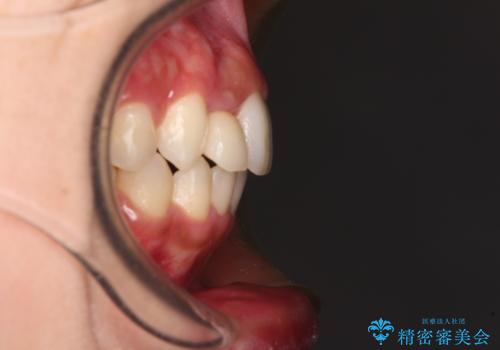

- 上下前歯のデコボコを気にして来院された患者様です。

前歯のセラミックが装着されている歯は、歯根が短くなっており、他院では抜けてしまうので矯正はできないと言われていたようです。

患者様と相談し、抜けてしまった場合にはインプラントあるいはブリッジによる補綴治療が必要となることを確認し、極力歯根に負担のかからないような仕上がりで治療を進めて行くこととしました。

デコボコを解消には、IPR(歯と歯の間を削る)をメインに歯列排列を設計し、インビザラインにて矯正治療を行うこととしました。

レントゲン写真上では、矯正治療前後で歯根長さに大きな違いはなく、抜歯を回避することができました。

上顎内側に転位している前から2番目の歯は移動が難しく、無理矢理歯根全体を動かそうと設計すると、歯肉退縮・歯髄壊死・歯根吸収といった危険性が増すため、無難なゴールにて治療を終えることとなりました。